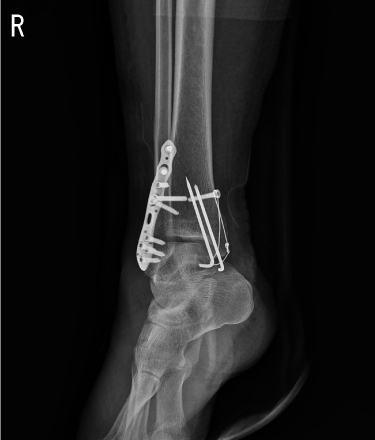

발목 골절

발목 골절은 심하게 접질리면서 발생하게 됩니다. 발목에는 안쪽과 바깥쪽으로 복사 뼈가 있고 중앙에 관절면을 이루는 경골과 거골이 마주하고 있는데 가장 흔한 골절이 내측 혹은 외측 복사뼈 골절입니다.

발목 골절에서 발생하는 문제점

□ 대부분 관절 내 골절로 체중이 작은 관절 면적에 집중되어 외상성 관절염 위험이 높음

□ 심하게 접질리면서 인대 혹은 관절 연골 손상이 동반

□ 발목은 혈류 공급에 취약해 연부 조직이 불량해지거나 수술 시 감염 발생 위험 높음

2016.08.22

2016.08.23